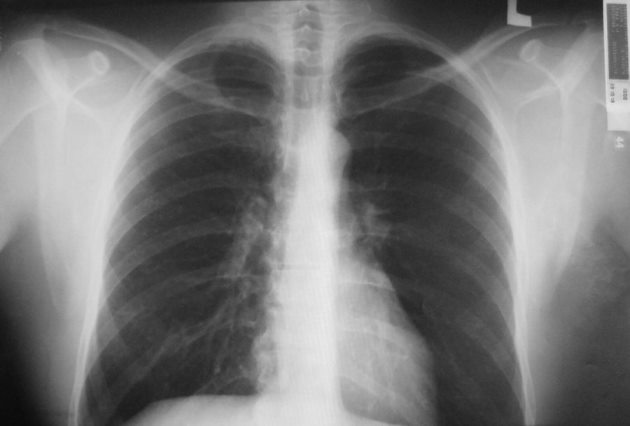

Онколог Астраханцев и рак легкого: вредное производство и курение

Онколог, заместитель главного врача по лечебной части клиники «Евроонко» Максим Астраханцев в беседе с каналом «RT на русском» назвал основную группу риска для заболевания раком легкого. Это курящие мужчины 50-60 лет, а также работники вредных производств. В первом случае большинство врачей соглашаются, что риск развития онкологии у курильщиков выше в 10-12 раз по сравнению с избегающими вредной привычки. На счет ряда производств, впрочем, существует полемика. Так, онколог Астраханцев упомянул в своем комментарии RT асбест, широко использующийся в России — из него изготавливают более 300 видов промышленной продукции. Казалось бы, столь вредное производство уже давно стоило бы запретить, но никак не утверждать распоряжением правительства (Постановление Правительства Российской Федерации от 31.07.1998 г. № 869) и уже тем более не защищать на самом высоком уровне. Правда, есть нюанс – в документе говорится только и исключительно о хризотиловом асбесте.